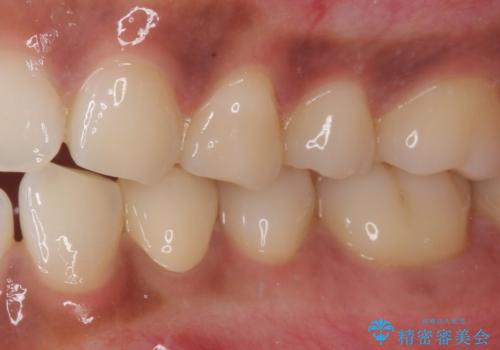

痛みでうずく 根管治療と補綴治療

- 下顎の小臼歯が食事などの度に痛みを感じるとのことで来院された患者様です。

レントゲン写真などで診査を行ったところ、左下の第一小臼歯の神経組織が壊死し、根尖部周辺の骨に炎症が認められました。

まずは根管治療を行い、症状が消退したことを確認してオールセラミッククラウンにて補綴治療を行うこととしました。